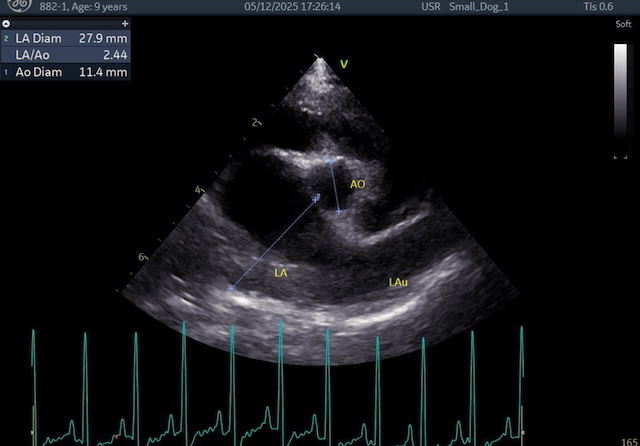

症例の術前所見は、僧帽弁の重度の逸脱があり、僧帽弁逆流量も多く、左心房の拡大および、左心室の拡大が酷かったのですが、

術前の所見↓